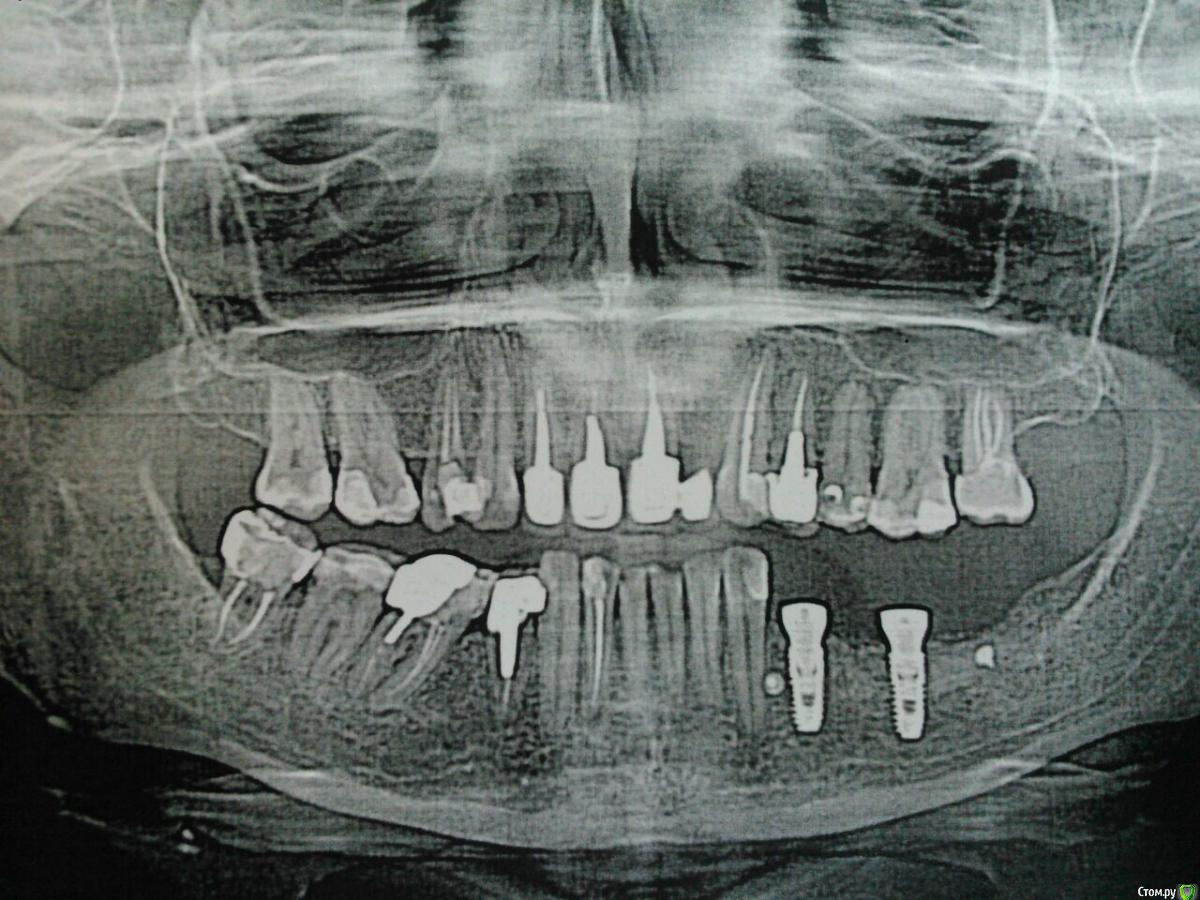

kamranchick Опубликовано 25 апреля, 2016 Поделиться Опубликовано 25 апреля, 2016 Пациентка обратилась с целью восстановления жевательного отдела.финансовый вопрос не интересует, хотелось бы чтобы с минимальными рисками.1.я думаю - удаление, 3 винта, сосидж, 5 пинов.чтобы вы предложили? Ссылка на комментарий

kamranchick Опубликовано 2 мая, 2016 Автор Поделиться Опубликовано 2 мая, 2016 ну я указал 3 сегмент, 3 винта, следовательно удаление 5 го зуба, установка имплантатов в область 35 36 и 37 Ссылка на комментарий

dantist_movani Опубликовано 2 мая, 2016 Поделиться Опубликовано 2 мая, 2016 ну я указал 3 сегмент, 3 винта, следовательно удаление 5 го зуба, установка имплантатов в область 35 36 и 37 так там и так 3.5 нет. Ссылка на комментарий

dantist_movani Опубликовано 2 мая, 2016 Поделиться Опубликовано 2 мая, 2016 Ось имплантата в проекции 3.7 слишком язычная, так же имплантат устанавливали? Ссылка на комментарий